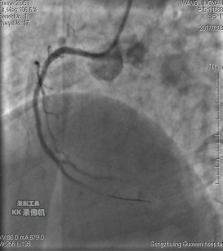

3月3日14時30分:經(jīng)右橈動脈行冠脈造影見:左主干未見明顯異常,TIMI血流3級,前降支開口正常,近中段20%狹窄,TIMI血流3級;回旋支開口正常,中遠(yuǎn)段75%狹窄,TIMI血流3級。右冠狀動脈開口正常,中段長病變,最重99%狹窄, TIMI血流3級。

圖1 回旋支遠(yuǎn)段70%狹窄 圖2 右冠脈中段99%狹窄

中日聯(lián)誼閆明洲教授向家屬交代病情及介入相關(guān)并發(fā)癥后,患者及家屬同意冠脈支架治療,過程順利,于右冠脈中段植入Firebird2 2.5*33mm 藥物洗脫支架1枚。

術(shù)前 術(shù)后